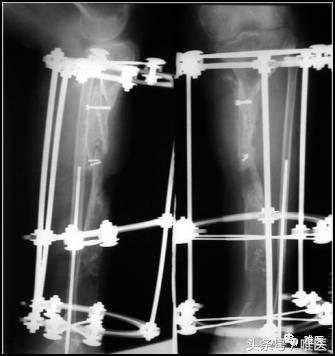

二期:一期术后6个月,两骨断端逐渐靠近、重叠到位后,再行左胫骨中上段断端修整、重叠对合,髂骨植骨螺钉固定,继续外架保护固定。

当两骨断段逐渐靠近接触后,二期行断端清理和修整,造成新鲜骨创面,并使断端良好对合,同时植骨,继续外架固定。